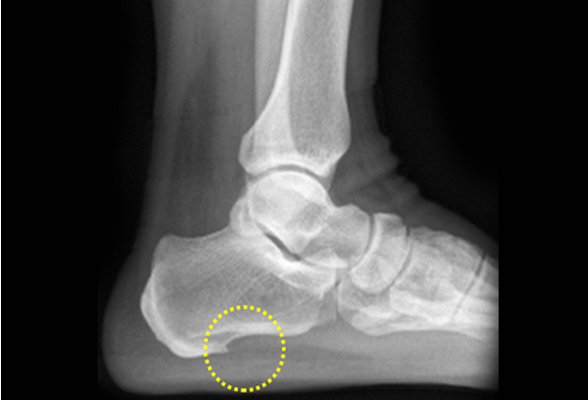

족저근막염

족저근막은 발뒤꿈치 뼈에서 시작하여 발가락 기저 부위에 붙은 두껍고 강한 섬유 띠로,

발의 아치를 유지하고 충격을 흡수하며 체중이 실린 상태에서 발을 들어 올리는데 도움을 줍니다.

이러한 족저근막에 염증이 발생한 질환을 족저근막염이라고 합니다.

비수술 치료 : 약물, 고정 (깁스 또는 보조기), 물리치료, 주사치료, 도수치료

수술치료 : 관절내시경